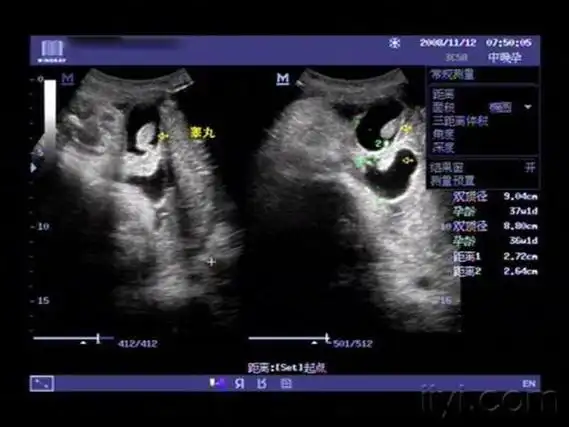

孕26周四维下睾丸的样子 如何看四维彩超识性别

四维彩超,两次发现貌似蛋蛋的两个对称的东西,中间间隔几分钟,再看